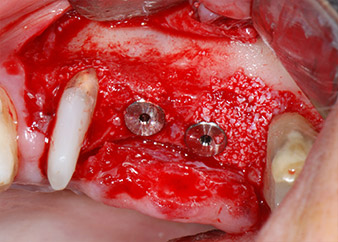

Dann wurden die Implantate (Restore, Keystone Dental) mit dem Implantatmotor eingesetzt (Abb. 11 und 12).

Insertion des Implantats an Position 26

Abb. 11: Insertion des Implantats an Position 26 bei geringer Geschwindigkeit und einer Drehmomentbegrenzung von 35 Ncm.

Eindrehen der Abdeckschrauben

Abb. 12: Beide Implantate sind in Position und bereit für das Eindrehen der Abdeckschrauben.

Knochendefizite an der mesialen Fläche des Zahns 27 und an der bukkalen Wurzel des Zahns 24 wurden mit xenogenem Knochenersatzmaterial aufgefüllt und mit einer resorbierbaren Kollagenmembran (Geistlich Bio-Gide) im Sinne einer GBR-Augmentation (Abb. 13 und 14) abgedeckt.